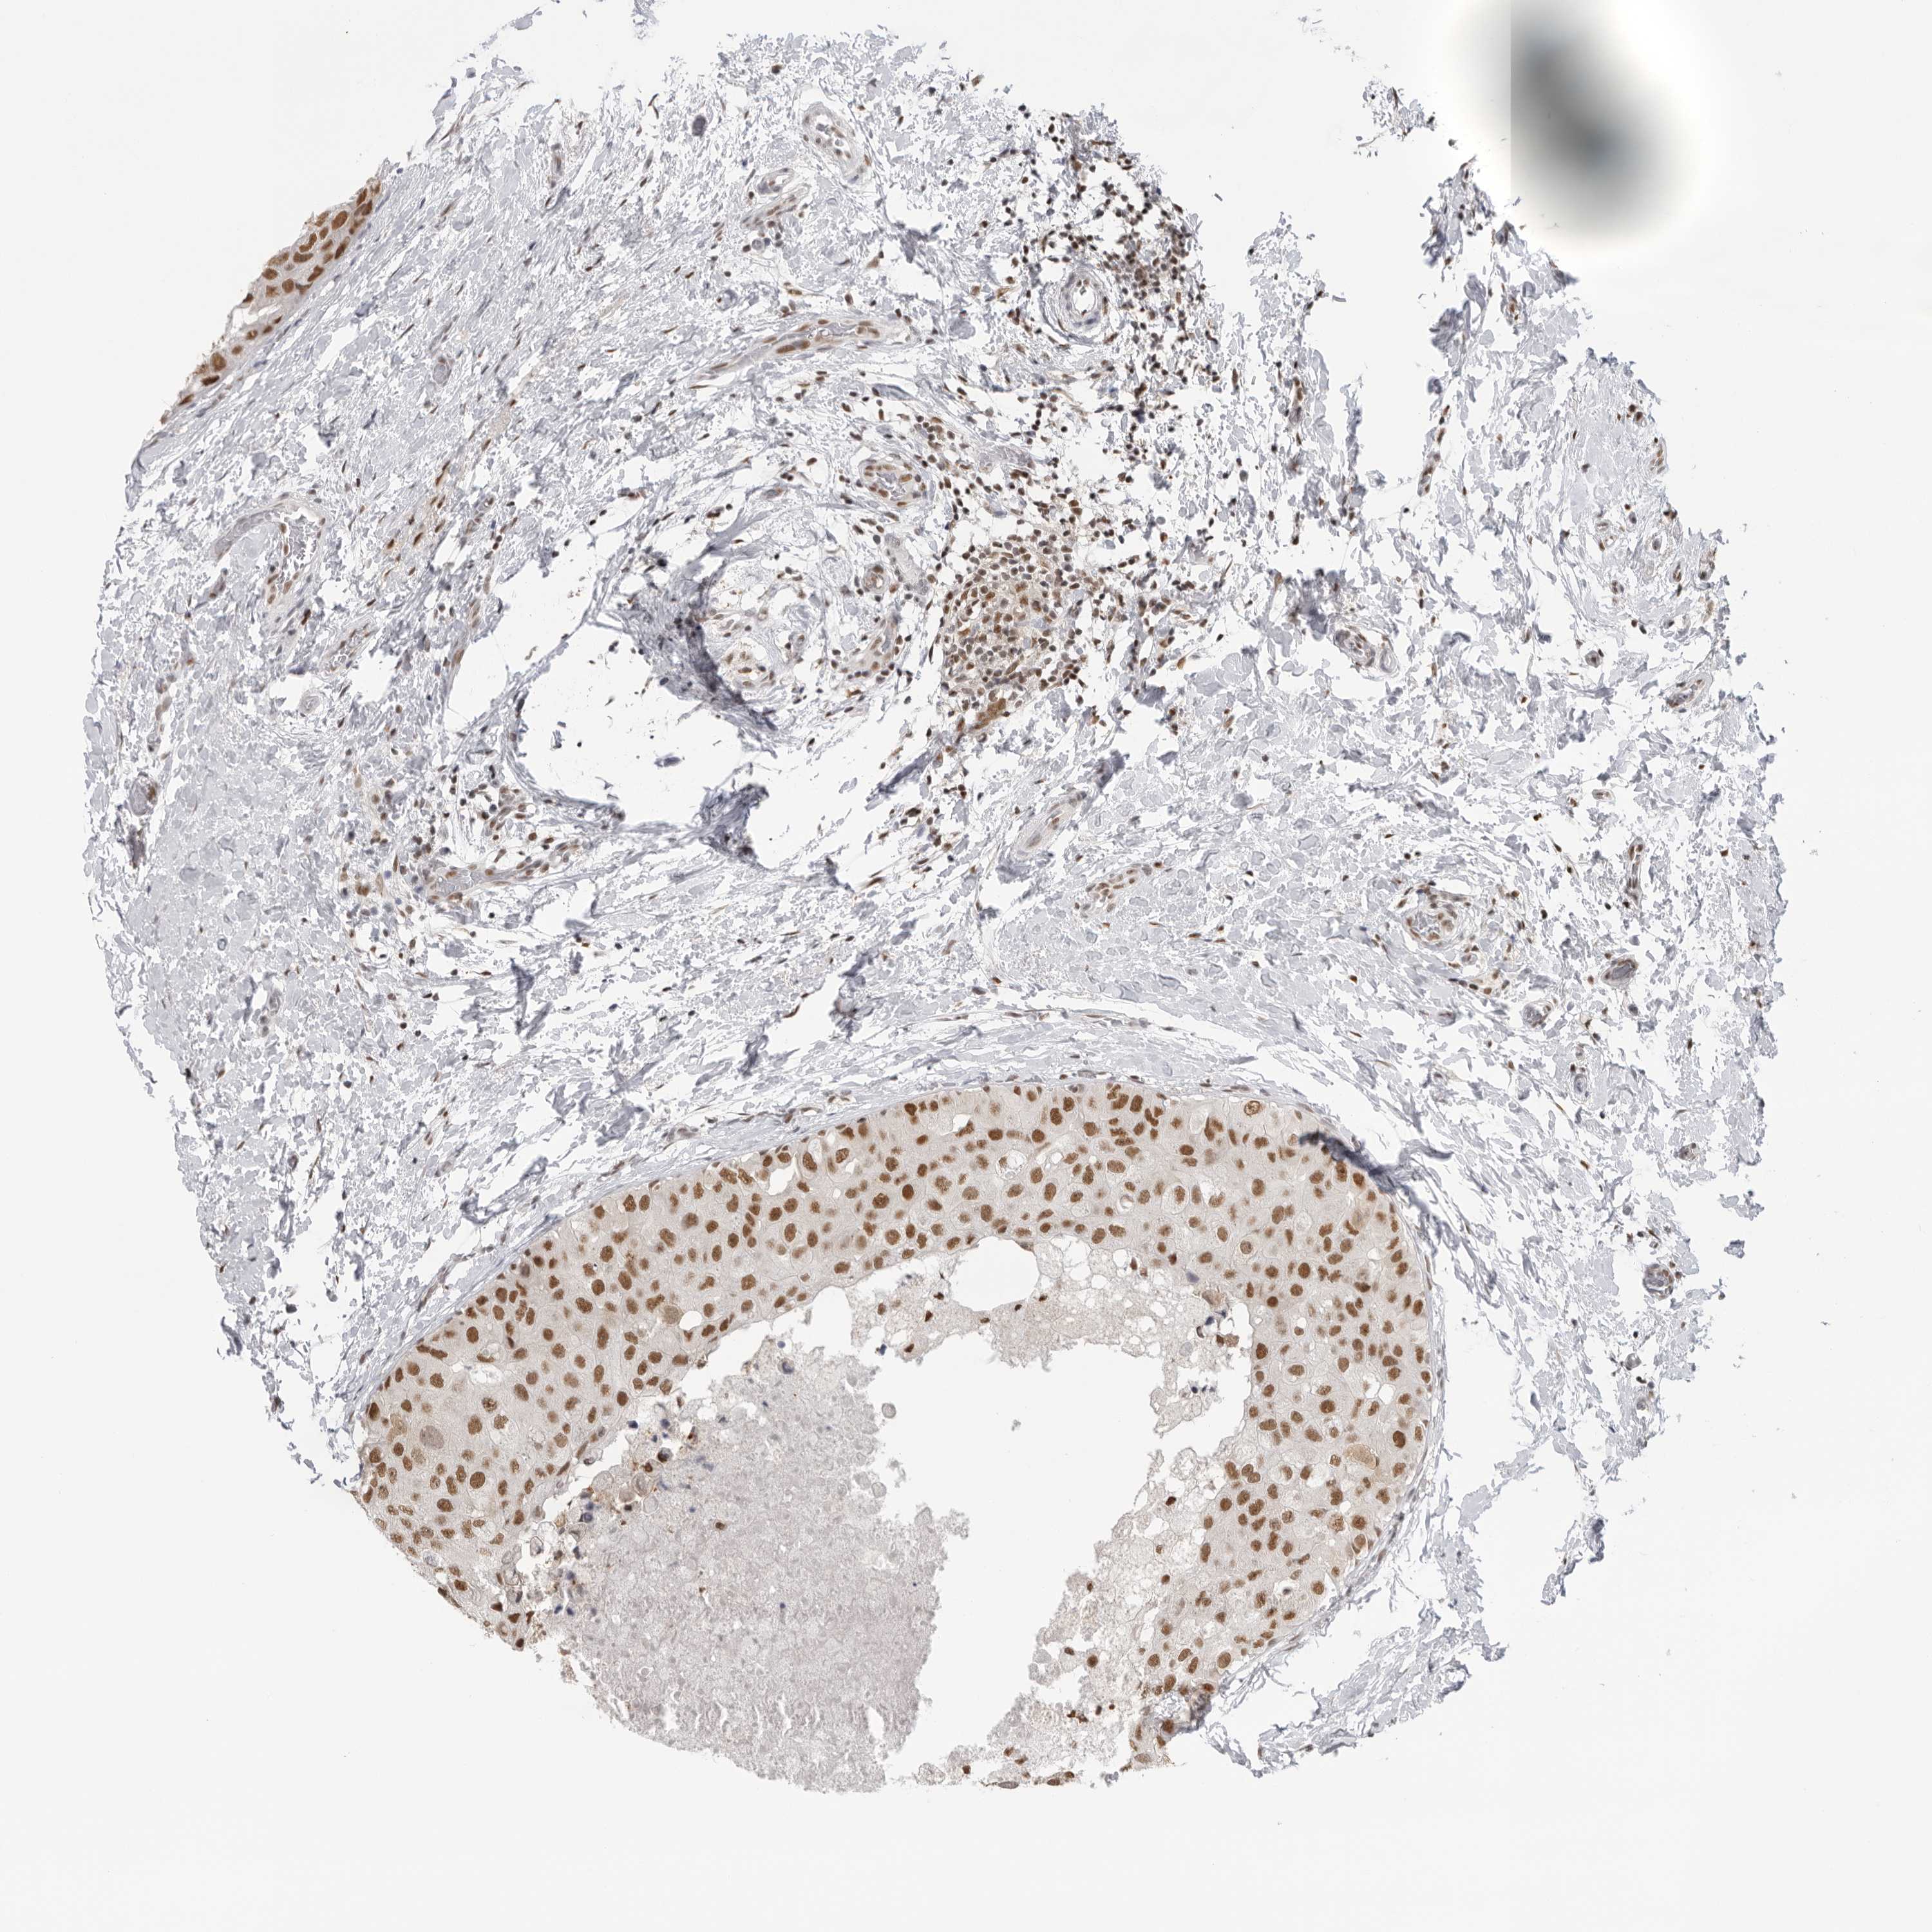

BRCA TCGA BRCA VALIDATION PROTEIN EXPRESSION

Breast cancer

Human cancer